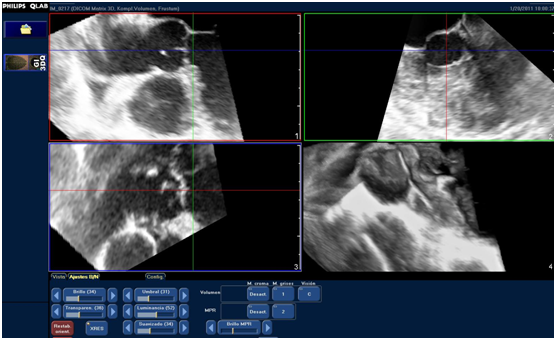

To assess the LVOT area, a QLAB 7.1 software (Philips Ultrasound) was used at a work station that was separated from the equipment. Upon exportation of the complete volume series to the work station, LVOT orthogonal cuts were performed, paying particular attention to achieving an angle of 90° with its long axis. Consequently, the references of the planes provided by QLAB (usually red and blue planes) were used, thus obtaining a short axis of LVOT in the third plane (green) (Figure 1).

Figure 1 Acquisition of LVOT orthogonal planes: LVOT long axis can be observed (red and blue planes) and its orthogonal view at the short axis (green plane). Measurement of the larger and shorter diameters and of LVOT area are obtained by planimetry of the short axis from the green plane.